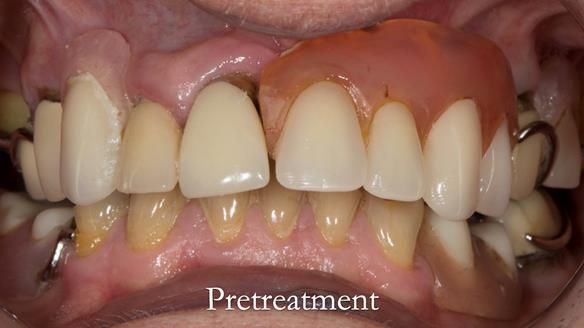

Aesthetically and functionally poor RPDs were replaced for Eileen, a 74 year old woman.

- Upper and lower metal based RPDs, poorly fitting, worn occlusal surface, reverse curve aesthetics, lacking support

- Poor dental appearance with reverse incisal curve

- The upper right central and lateral incisors with post crowns. Healthy and functionally secure but with poor appearance, contributing to the reverse curve.

- Moderate to heavily restored dentition with deep overbite (Class 2 div II)

- Yellowish lower front teeth with small amount of wear.

- The lower right canine (LR3) is worn with MOD cavity.